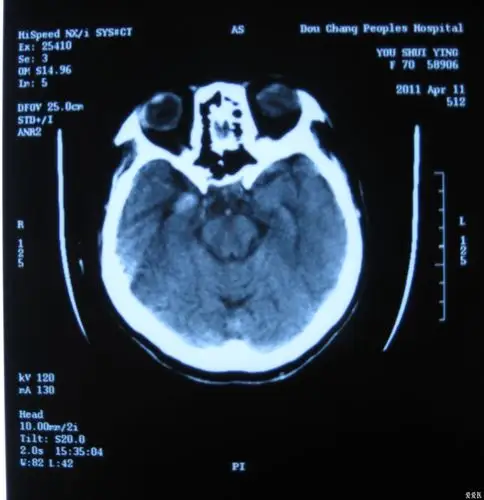

高血压脑出血的微创治疗